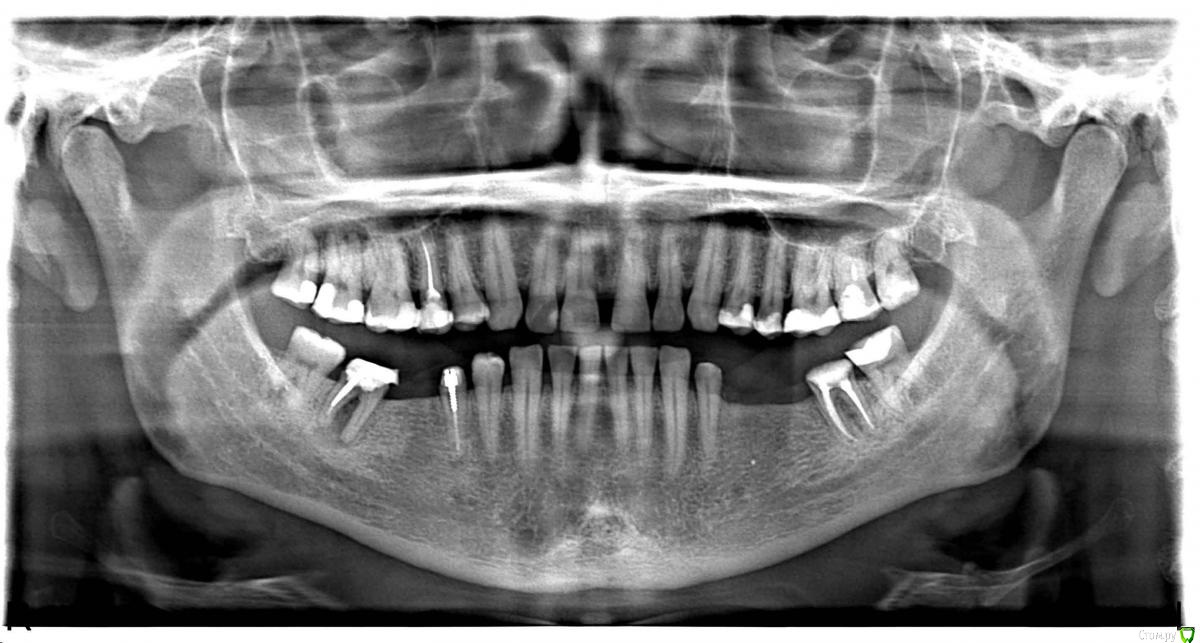

Некий Опубликовано 27 апреля, 2017 Поделиться Опубликовано 27 апреля, 2017 Добрый день!Ранее ношенные "мосты" прохудились и ушли в утиль.Сейчас стоит вопрос принятия "правильного" решения.ОПТГ был сделан еще в ноябре 16г.С тех пор произошли изменения:47 - удален. Заживал очень долго. Несколько раз удалялись секвестры.45 - делается под вкладку. Снимок прилагаю.37 - был сильно разрушен. Восстановлен ниже уровня десны на 3 штифтах. Снимок до восстановления.Доктор предлагает 2 "моста": 34-37 и 45-48. Напрягает состояние 37 и 45 зубов.1. Не получу ли в самое ближайшее время после установки мостов проблемы?2. Не сильно ли углублен канал под вкладку у 45го? Затемнение под корнем - это ни какая-либо проблема?3. Какие еще варианты могут быть при данной ситуации? Большое спасибо за Вашу помощь! Ссылка на комментарий